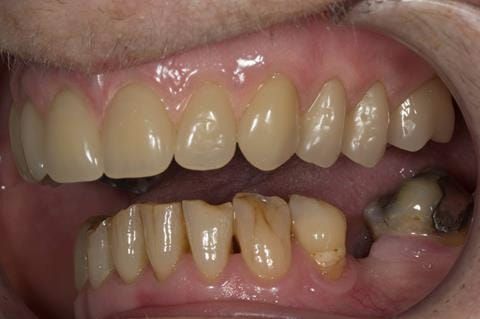

- Poorly fitting cobalt chromium based maxillary partial denture, which has been added to. This exhibited poor retention, stability and tissue fit (support). Unable to wear a new acrylic based denture.

- UR7 - occlusal amalgam. 10- 20% alveolar bone loss. Healthy periodontium with reduced attachment level. No mobility.

- Eight mandibular anterior teeth worn incisal edges from now extracted maxillary anterior crowns. Gingivitis - owing to inadequate oral hygiene.

- LL6 with large amalgam restoration - healthy periodontium.

- Bruxism.